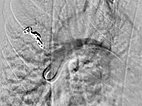

A guiding sheath was inserted into the right pulmonary artery from the neck (transjugular) via the heart, and a coaxial catheter was inserted through this by the Seldinger technique. After injection of contrast medium, pulmonary AVMs are also seen in the right lower lobe of the pulmonary circulation.

After cannulization of the larger pulmonary AVM, dilatation of the direct arteriovenous communication in the form of an aneurysm is seen. This is typical of Osler’s disease. The venous outflow is dilated, thus the risk of thromboembolism is particularly high.